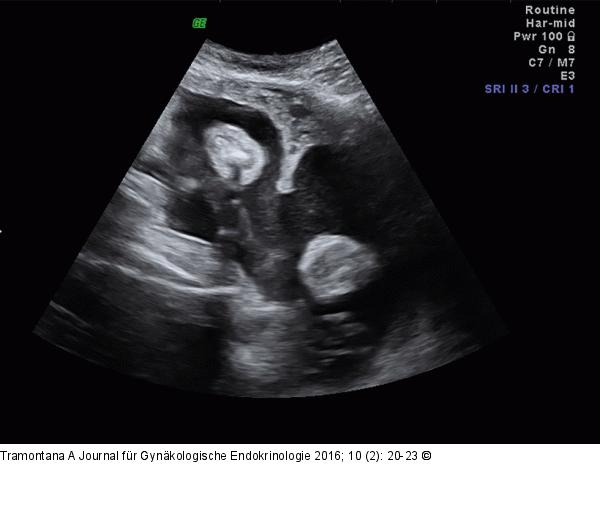

Abbildung 2: Uterus subseptus

Sonographische Darstellung des Uterusseptums bei intakter Schwangerschaft. |